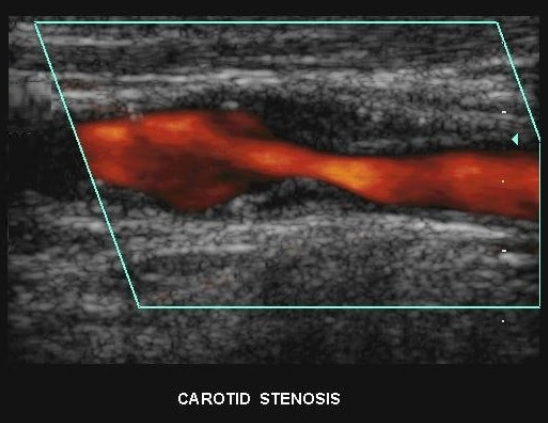

Patient presents to ultrasound department for preoperative work-up. Patient scheduled to have coronary artery bypass graft (CABG) in two days. Patient has HX of peripheral vascular disease, smoking, HTN and hyperlipidemia. You obtain this image. Consider following questions.

1. Is it possible to have plaque producing stenosis without symptoms?

2. What are the risk factors for atherosclerosis in this patient presentation?

3. Is this image diagnostic for hemodynamically significant stenosis? Why or why not.

Yes

Hx of peripheral vascular disease, smoking, HTN, hyperlipidemia. (Also has CAD because they are here for pre op for CABG)

No because power doppler only shows presence of flow and no velocity information